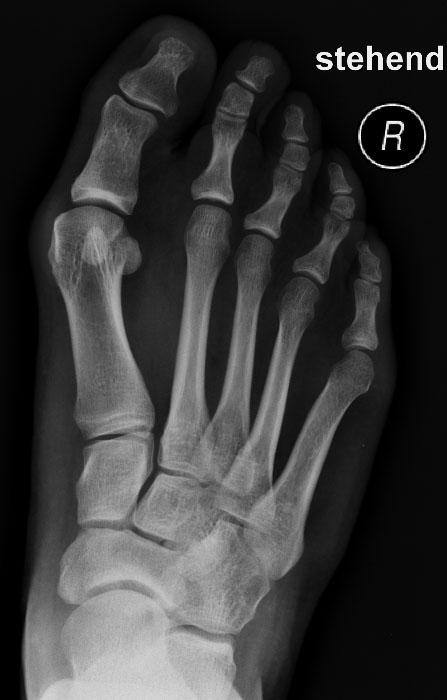

• Fehlstellung von Gelenken

(O-Beinstellung, Senk-/Spreizfuß, Hammerzehen)